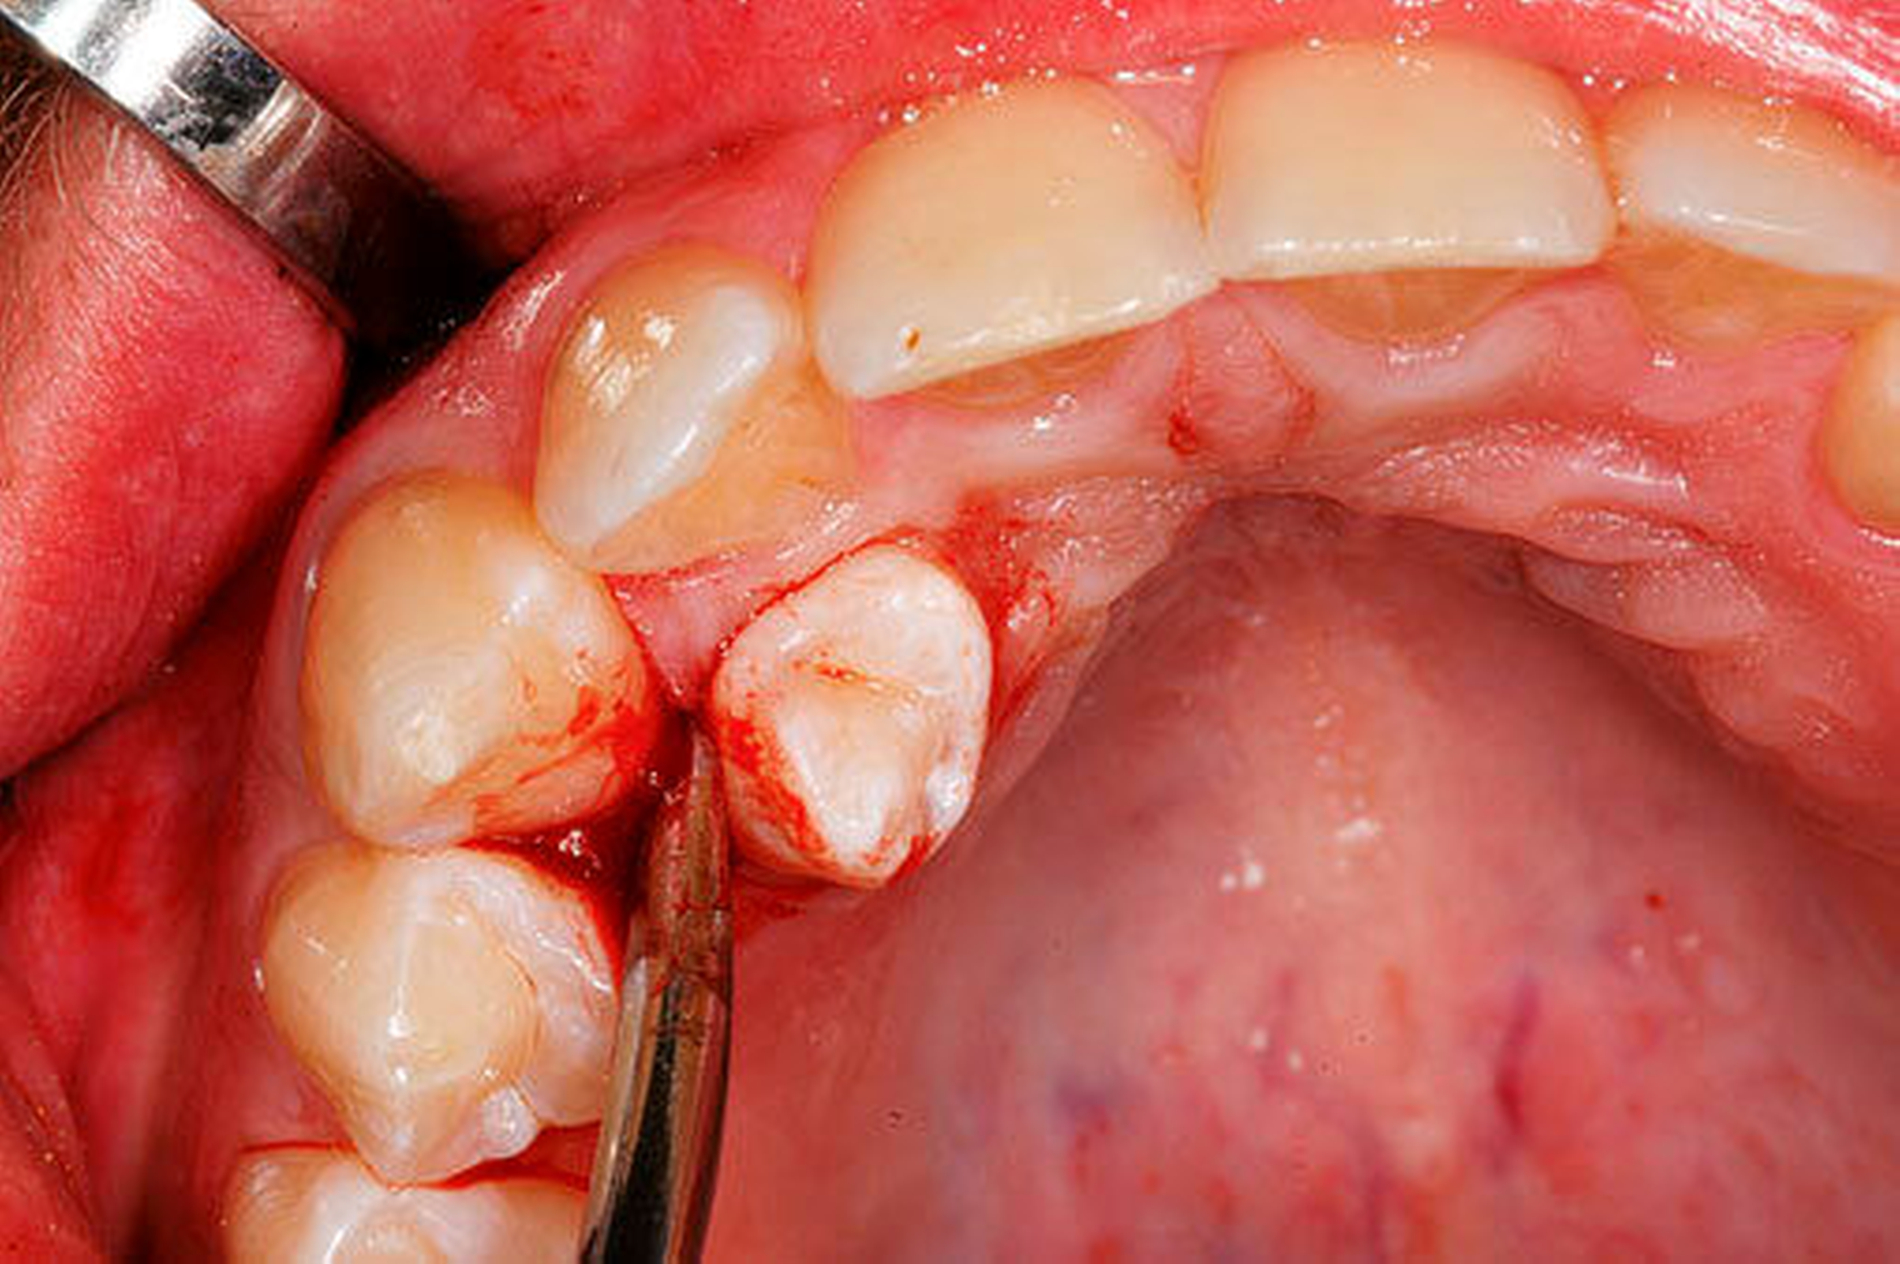

wenn der überzählige Zahn in die Mundhöhle durchgebrochen ist [Garvey et al. 1999] (Abbildung 2).

die operative Entfernung von überzähligen Zähnen geht in der Regel mit einer geringen Komplikationsrate und einer guten Prognose einher (Abbildungen 3 und 4) [Primosch, 1981].